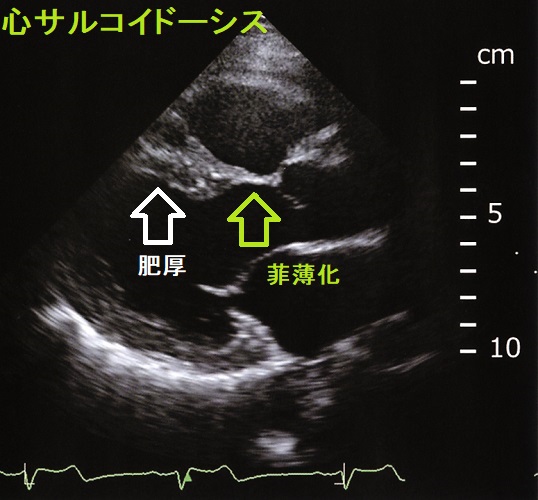

心臓MRI,Ga シンチ・Tl シンチ・FDG-PETで診断。PET-FDG は最も診断能が高く、感度89%、特異度78%。甲状腺の病変が同時に見つかる場合もあります。[ FDG-PET/CTと甲状腺腫瘍・橋本病(慢性甲状腺炎)][Am J Cardiol. 2015 Nov 15;116(10):1581-5.]

心筋生検で確定。

心機能低下する前にステロイドを開始すれば生命予後改善を見込める、迅速に正しく診断するのが重要。

心室頻拍(VT)を起こしていれば、ステロイドに併用して植え込み型除細動器(ICD)